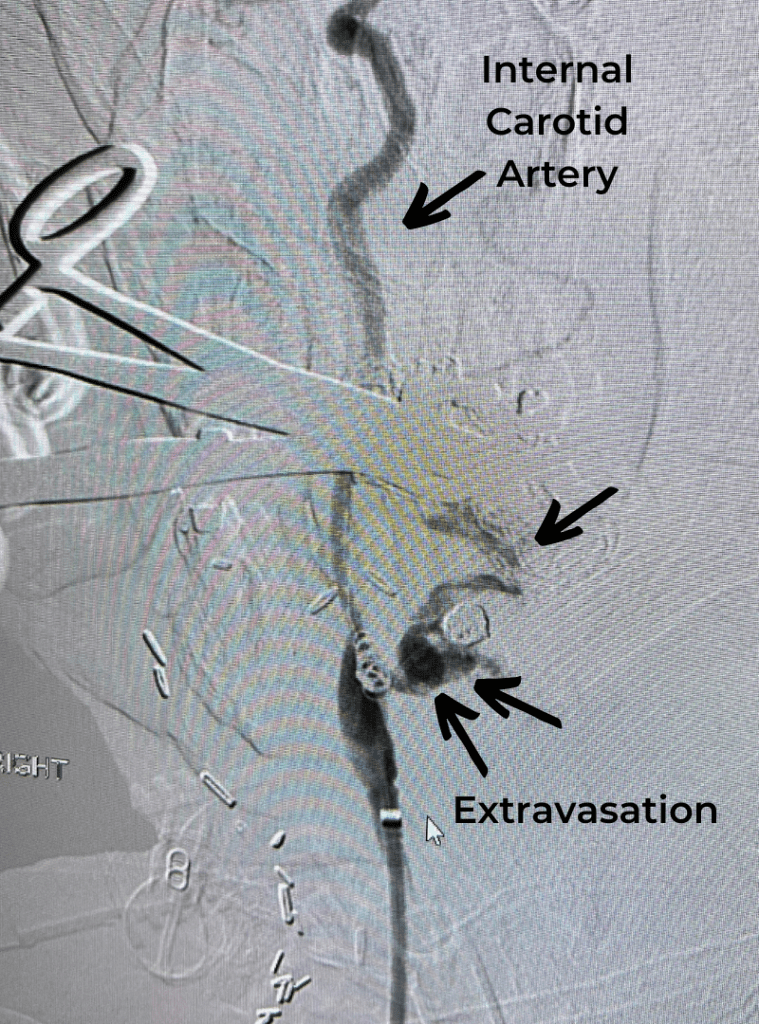

Endovascular:

CME:

Direct Carotid Cavernous Fistula (CCF)

Author: Jonathan L. Brisman M.D., F.A.C.S., Read More!